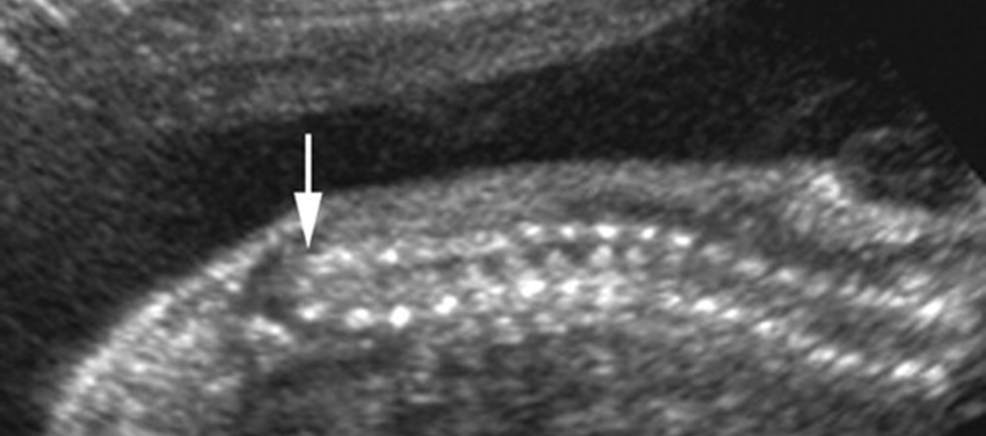

Hydronephrosis

UPJ Obstruction